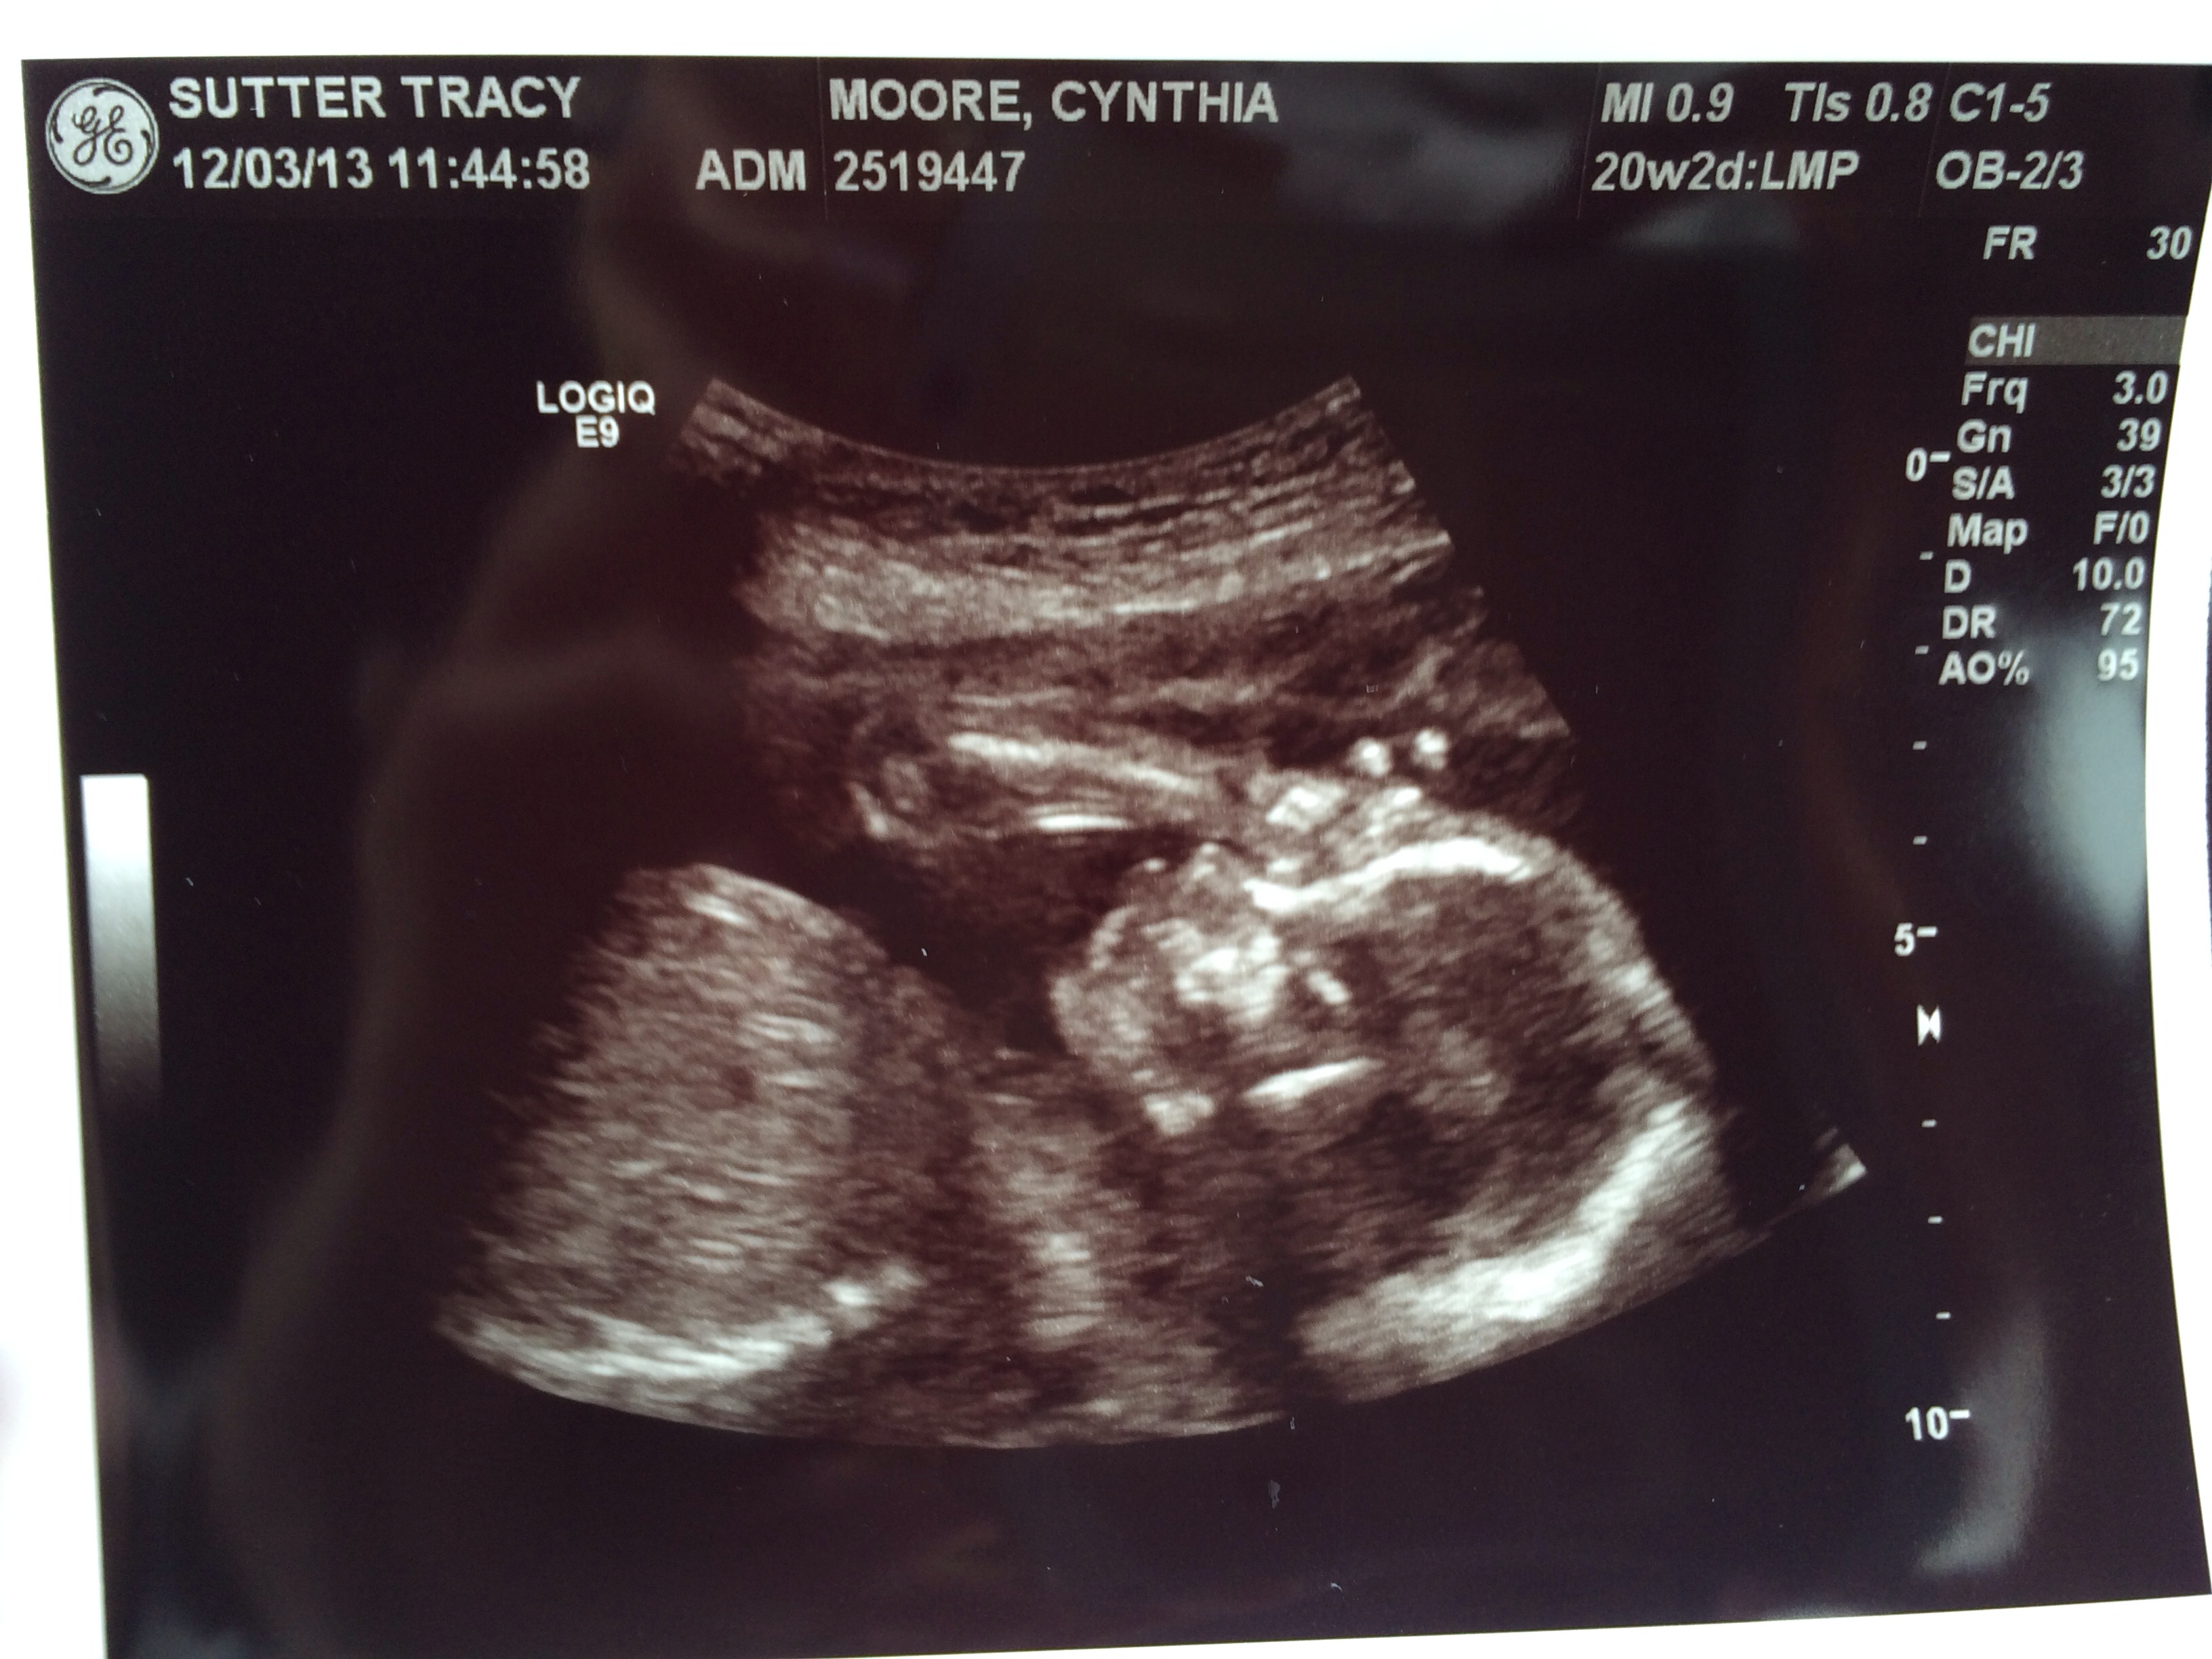

UPDATED through 12/6: Week of 12/2 Anatomy Scan

• @bethy84 Well, dang! Even if you didn't already know it was a boy, it doesn't get more obvious than that!

• What a money shot!! Our elective scan was sooo blurry I'm hoping for a much clearer picture before looking at those baby blue paint swatches ;)

• @Nijay714 YES!! Congrats on your girl!!